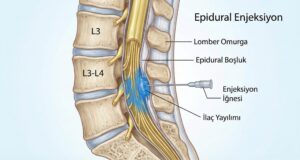

Karpal tünel sendromu tedavisi seçenekleri:

-

El bileği ateli kullanımı

-

İlaç ve enjeksiyon tedavileri

-

Aktivite düzenlemesi

-

Fizik tedavi uygulamaları

-

Cerrahi tedavi (ileri vakalarda)

Özellikle ileri evrelerde, cerrahi müdahale ile sinir üzerindeki baskı kalıcı olarak ortadan kaldırılabilir. Ancak doğru zamanlama burada çok önemlidir.